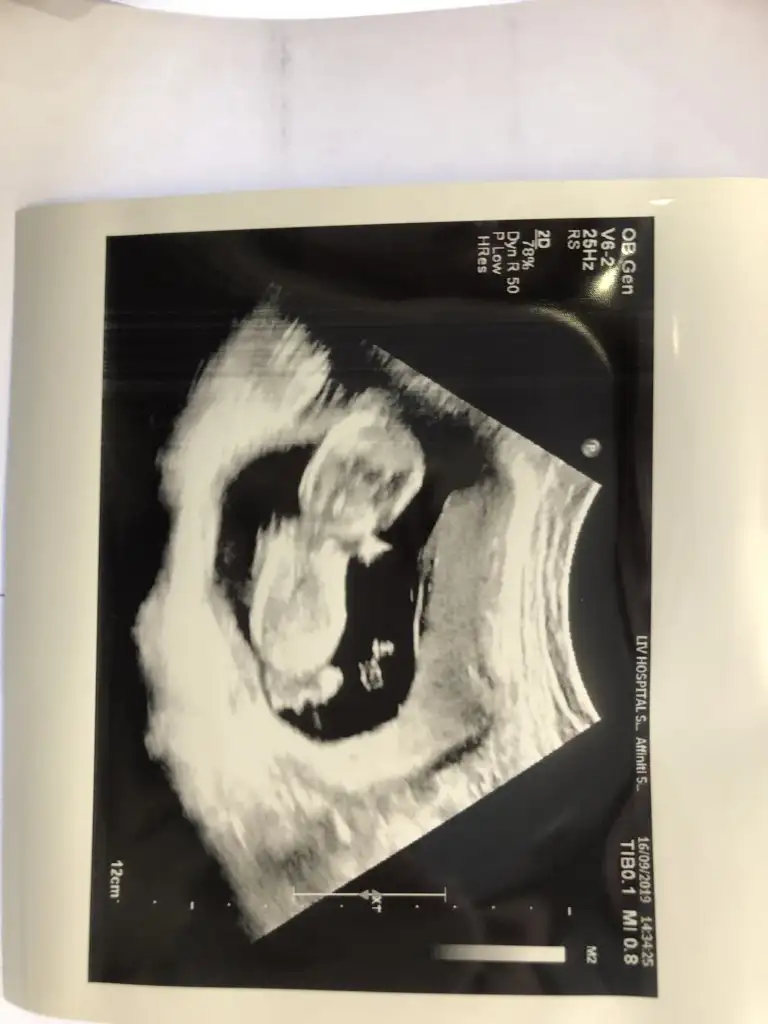

Erkek mi?Merhaba bize de tahminde bulunabilir misiniz? Karından usg

Kaç haftalık tam net degil başka varsa tahmin ederimMerhaba benim için de cinsiyet tahmini yapabilir misiniz?